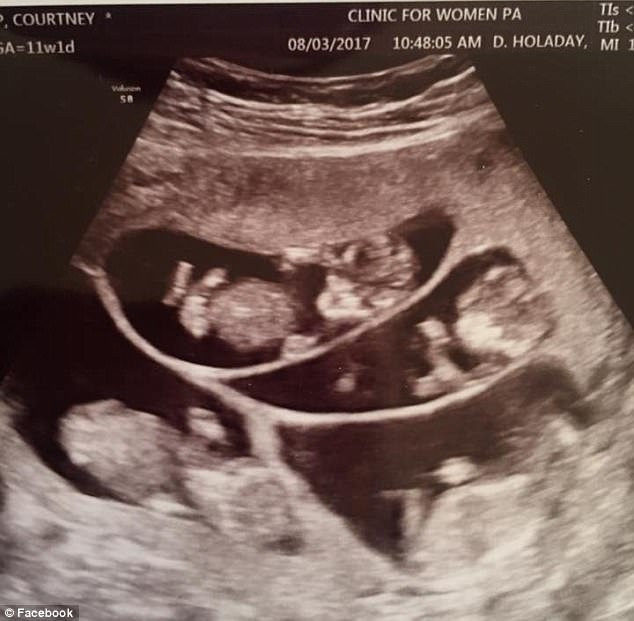

Trong lần mang thai này, khi các bác sĩ tiến hành siêu âm, họ đã nghe thấy tiếng của 6 trái tim trong bụng của Courtney và đi đến kết luận cô mang thai 6 và nguy cơ sinh non là rất cao.

Hình ảnh siêu âm ban đầu cho thấy 3 bào thai

Lần siêu âm sau đó cho thấy có tới 6 đứa trẻ nằm trong bụng người mẹ này